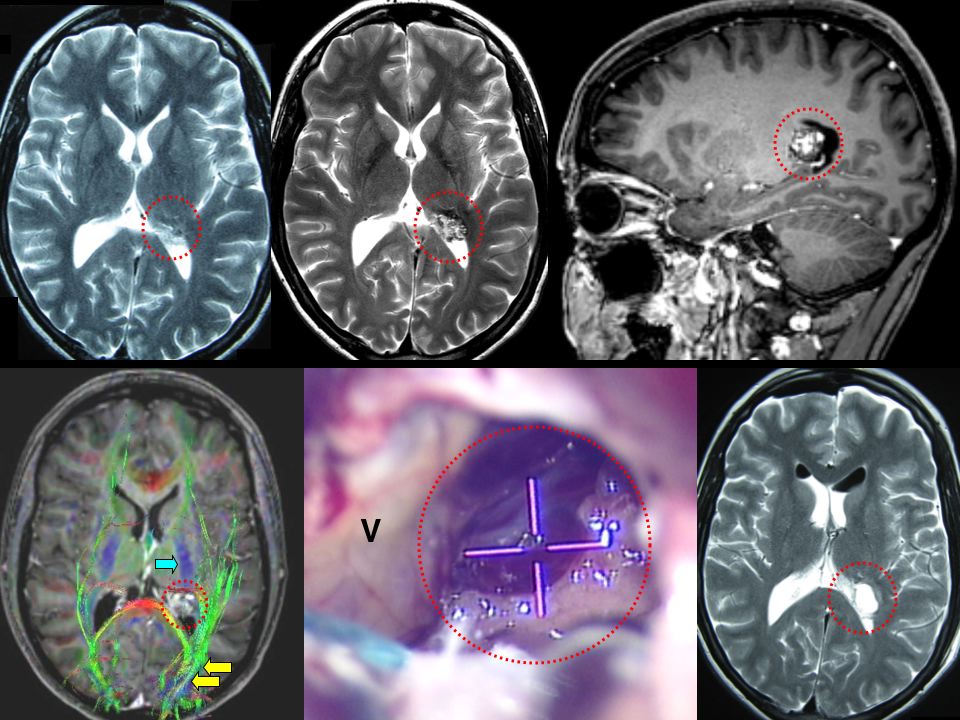

Мр картина венозной ангиомы левой гемисферы мозжечка - 96 фото